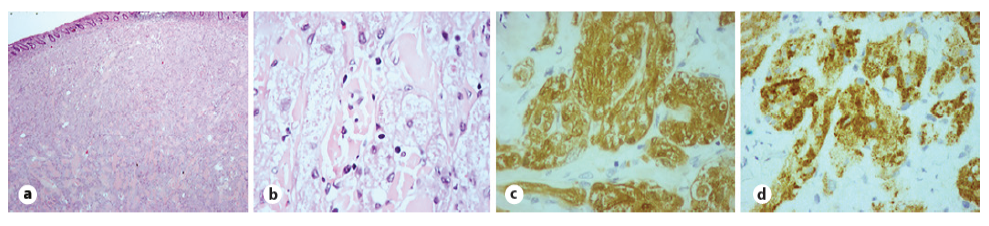

Histological evaluation revealed a solid neoplasia of the submucosa consisting of epithelioid cells of vast granular citoplasma, centered by small, round, uniform nuclei (Fig. 3a, b). These cells were positive for S100 and inhibin - granular cell tumor (GCT) (Fig. 3c, d). The lesion was limited to the submucosa and was covered by normal colonic mucosa. The excision margins were free. A surveillance colonoscopy at 12 months is currently scheduled.

Fig. 3 Histological evaluation. a Submucosal expansion by epithelioid cells, covered by normal colonic mucosa (×20 magnification). b These cells have vast granular citoplasma, centered by small, round, uniform nuclei (×100 magnification). c, d Immunohistochemistry showing positivity for S100 (c) and inhibin (d) (×400 magnification).